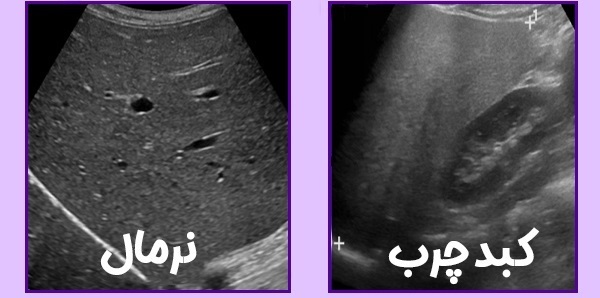

سونوگرافی: یکی از رایجترین روشها برای شناسایی تجمع چربی در کبد